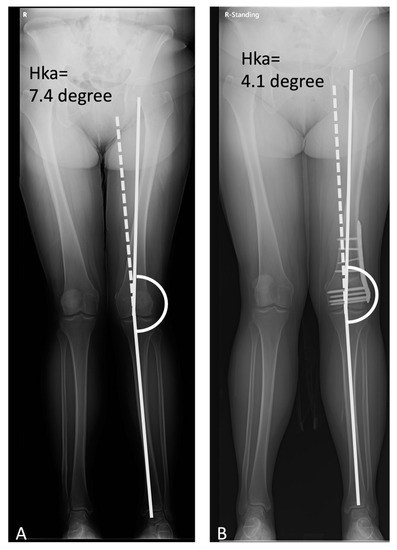

| MAD (mm) | −28.77 ± 12.98 | −9.45 ± 7.36 * | −14.6 ± 8.7 * |

| Hip-knee angle (degree) | 7.64 ± 3.62 | 2.58 ± 1.93 * | 3.2 ± 1.63 * |

| mLDFA (degree) | 83.51 ± 3.48 | 92.01 ± 3.41 * | 90.2 ± 2.77 * |